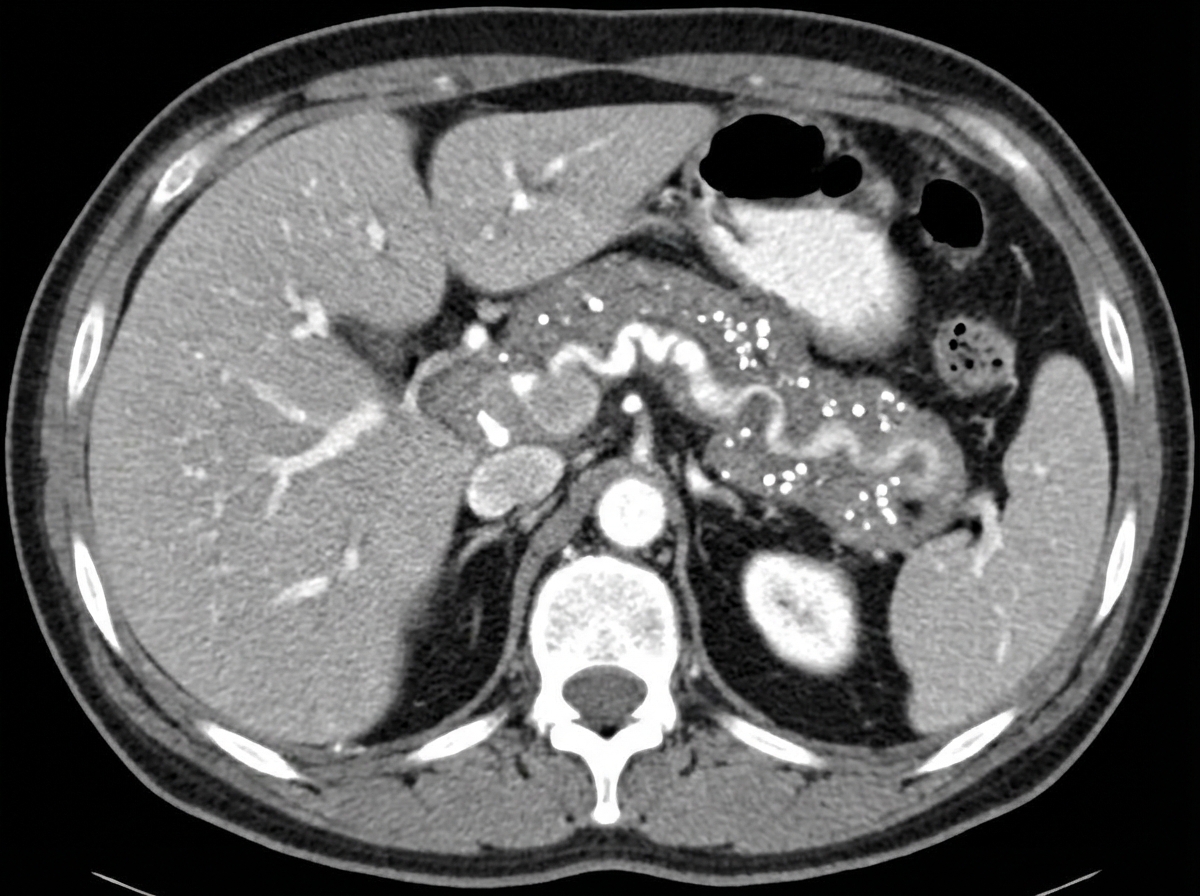

A 30-year-old known alcoholic patient presented with severe abdominal pain. On examination, a rigid abdomen is noted. The patient has a history of multiple episodes of abdominal pain over the last 4-5 years and has lost 5 kg of weight in the past 6 months. Serum lipase and amylase levels are normal. CECT abdomen was performed. What is the most likely diagnosis?

Explanation: ***Chronic pancreatitis*** - **Chronic alcohol use** with recurrent abdominal pain episodes over **4-5 years** and **weight loss** are classic features of chronic pancreatitis with **pancreatic insufficiency**. - **Normal serum lipase and amylase** levels are typical in chronic pancreatitis due to **pancreatic atrophy** and loss of enzyme-producing cells, unlike acute pancreatitis. *Acute pancreatitis* - Would typically present with **markedly elevated serum lipase and amylase** levels, which are normal in this case. - Usually has an **acute onset** rather than the chronic, recurrent pattern described over **4-5 years**. *Adenocarcinoma of pancreas* - More commonly affects patients **>60 years old** and presents with **painless jaundice** rather than recurrent abdominal pain. - **Weight loss** occurs but is usually more **rapid and severe**, and the **rigid abdomen** is less characteristic. *Periampullary carcinoma* - Typically presents with **obstructive jaundice**, **pale stools**, and **dark urine** due to **biliary obstruction**. - **Painless jaundice** is the hallmark feature, not the chronic abdominal pain pattern seen here.

Explanation: ### Explanation The diagnosis of acute pancreatitis requires at least two of the following three criteria: characteristic abdominal pain, serum amylase or lipase levels $\geq 3$ times the upper limit of normal, and characteristic findings on cross-sectional imaging (CT/MRI). **Why Serum Lipase is the Correct Answer:** Serum lipase is considered the **most diagnostic** and preferred biochemical marker because it is more **specific** to the pancreas than amylase. While amylase levels return to normal within 3–5 days, lipase remains elevated for 7–14 days, making it more useful for patients presenting late. Furthermore, lipase is more sensitive in cases of alcoholic pancreatitis and hypertriglyceridemia-induced pancreatitis, where amylase levels may be falsely low or normal. **Analysis of Incorrect Options:** * **Serum Amylase:** Although widely used and rises early (within 6–12 hours), it lacks specificity. It can be elevated in various non-pancreatic conditions like salivary gland disease, bowel obstruction, and ectopic pregnancy. It also has a shorter half-life. * **Serum P-isoamylase:** This is more specific than total amylase as it isolates the pancreatic fraction; however, it is not routinely available in clinical practice and does not surpass the diagnostic utility of lipase. * **Serum LDH:** LDH is a marker of systemic inflammation and tissue necrosis. While it is a component of the **Ranson Criteria** used to predict the **prognosis** and severity of pancreatitis, it has no role in the primary diagnosis. **High-Yield Clinical Pearls for NEET-PG:** * **Most specific imaging:** Contrast-Enhanced CT (CECT) is the gold standard for assessing complications (necrosis), but it is best performed **72 hours after** symptom onset. * **Early prognostic marker:** Rising Hematocrit or BUN levels are excellent early indicators of severity. * **Urinary Trypsinogen-2:** A highly sensitive bedside screening test for acute pancreatitis.

Explanation: ### Explanation **Correct Answer: B. Pancreatitis** A **pancreatic pseudocyst** is a localized collection of fluid, pancreatic enzymes, and necrotic debris surrounded by a wall of granulation tissue (lacking a true epithelial lining, hence "pseudo"). 1. **Why Pancreatitis is Correct:** Chronic and acute pancreatitis are the leading causes of pseudocysts. In **chronic pancreatitis**, they occur in approximately 20–40% of cases due to ductal obstruction or leakage. In **acute pancreatitis**, they typically develop 4–6 weeks after the initial episode as a complication of ductal disruption or peripancreatic fluid collections. 2. **Why Incorrect Options are Wrong:** * **Carcinoma of the pancreas:** While tumors can cause ductal obstruction leading to distal cysts, they are a rare cause of pseudocysts compared to inflammatory conditions. * **Trauma:** Blunt abdominal trauma (e.g., handlebar injuries in children) is the most common cause of pseudocysts in the **pediatric population**, but it ranks second to pancreatitis in adults. * **ERCP:** Post-ERCP pancreatitis can lead to a pseudocyst, but this is a specific iatrogenic subtype and not the most common overall cause. ### NEET-PG High-Yield Pearls * **Definition:** Requires **>4 weeks** to develop (to allow for the formation of the fibrous wall). * **Most Common Site:** The **lesser sac** (omental bursa), posterior to the stomach. * **Diagnosis:** **CECT** is the gold standard investigation. * **Management:** Most small (<6 cm) and asymptomatic cysts resolve spontaneously. * **Surgical Indication:** If symptomatic or complicated (infection, hemorrhage, or gastric outlet obstruction), internal drainage is preferred (**Cystogastrostomy** or **Cystojejunostomy**). * **Biochemical Marker:** High amylase levels in the aspirated fluid.